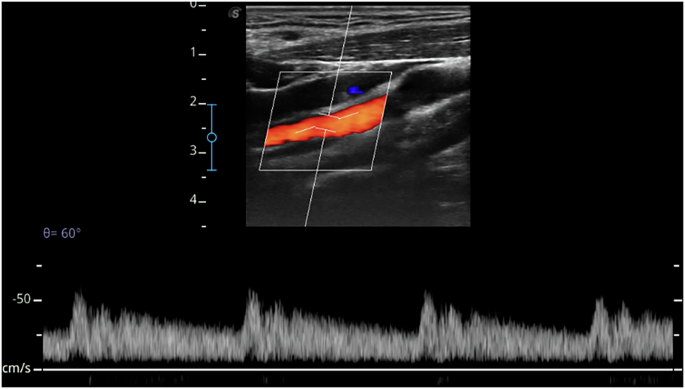

The key hemodynamic parameters, including Vs, Vd, and Vm-max, were extracted from the blood flow data (Fig. 6). Vs (cm/s) represents the peak blood flow velocity during systole, whereas Vd (cm/s) corresponds to the blood flow velocity at the end of diastole. Both values were calculated as averages over multiple cardiac cycles and automatically derived from blood flow data. \({\rm{Vm}}-\max ({\rm{cm}}/{\rm{s}})={\int }_{{\rm{i}}=1}^{{\rm{n}}}{{\rm{v}}}_{{\rm{i}}}/{\rm{n}}\), where Vi is the peak blood flow velocity at each sampling point during a cardiac cycle, and n is the number of sampling points. Vm-max represents the average peak flow velocity over the cardiac cycle, integrating both the systolic and diastolic phases. When multiplied by a correction factor of 0.5, Vm-max approximates the mean blood flow velocity (Vm), in cm/s. BFV, defined as the volume of blood passing through a specific vessel cross-section per minute, was calculated as \({\rm{BFV}}({\rm{ml}}/\min )={\rm{\pi }}\times {\left({\rm{D}}/2\right)}^{2}\times {\rm{Vm}}\times 60/100\), with D in mm. Total intracranial blood flow was determined as the sum of the blood flow from the bilateral ICAs and VAs.

Hemodynamic features of the ICA from a left ICA ultrasound Doppler image of the participant. ICA internal carotid artery.